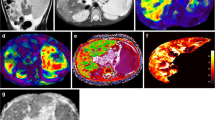

Representative images of the quantitative MRI sequences assessed in this study are provided in Fig. 1.